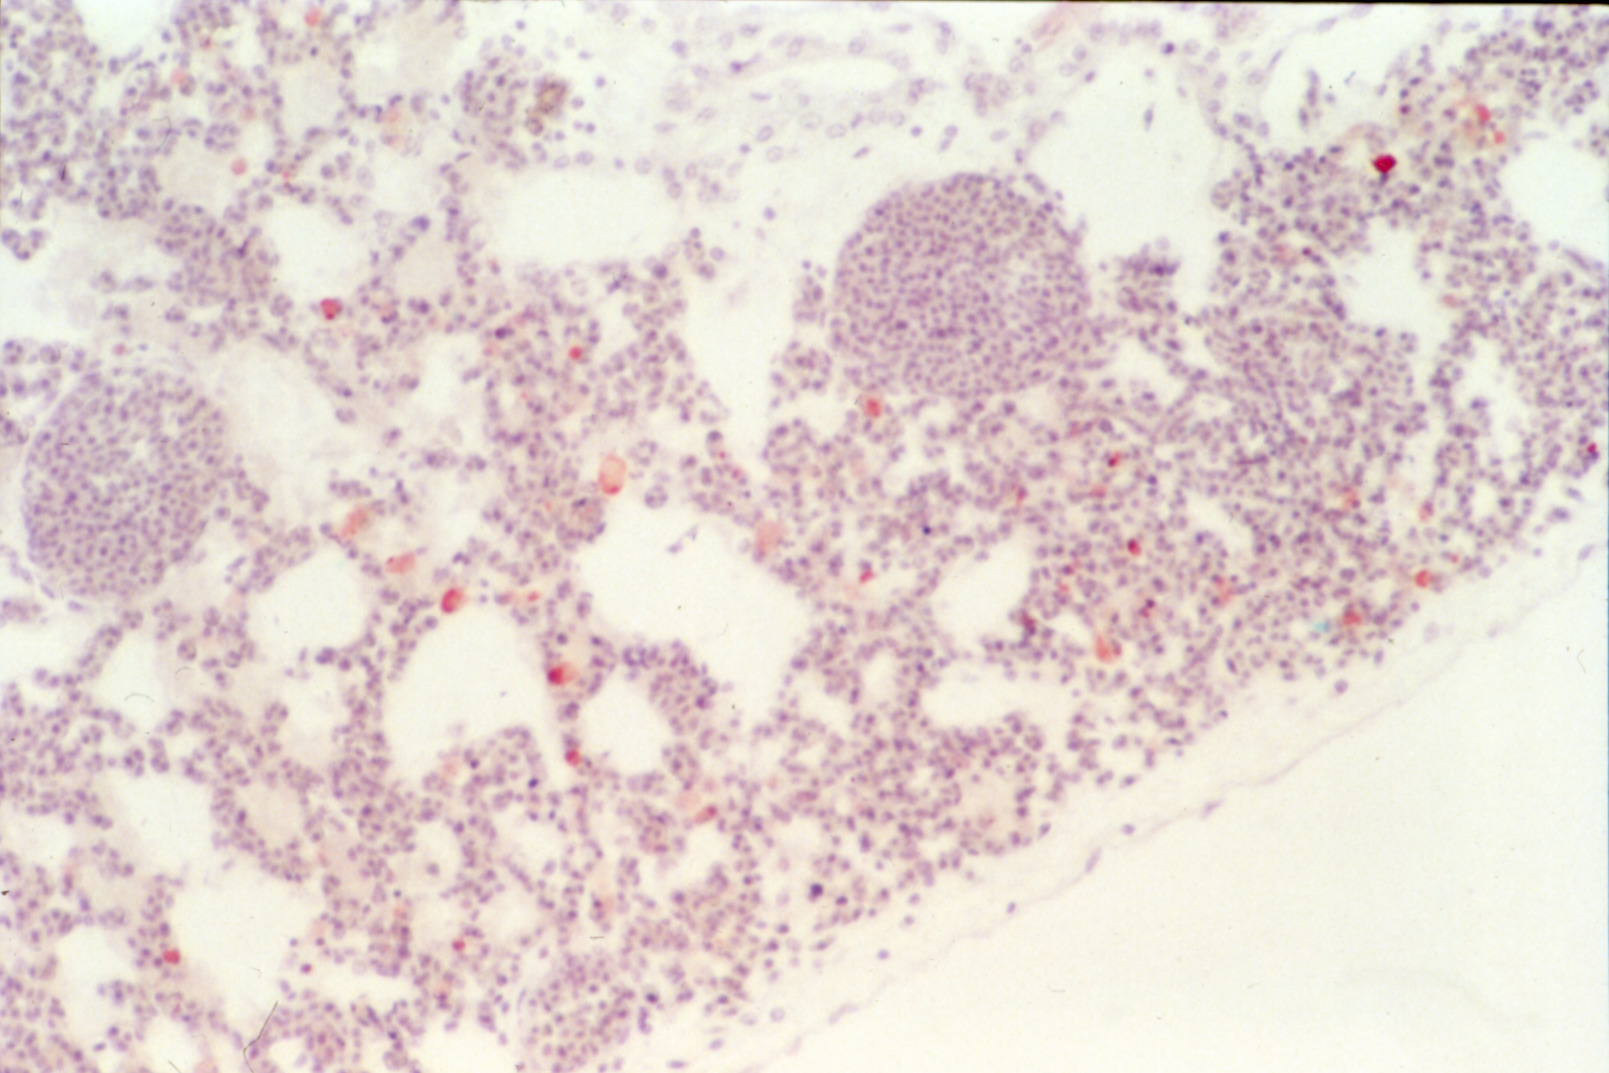

Marble spleen disease of ring-necked pheasants (slide study set no. 17) Item Info

Marble spleen disease of ring-necked pheasants (slide study set no. 17)

Poultry--Diseases Spleen--Diseases Ring-necked pheasant

Slide Study Set #17, Marble Spleen Disease of Ring-Necked Pheasants (includes 20 color slides), 1992